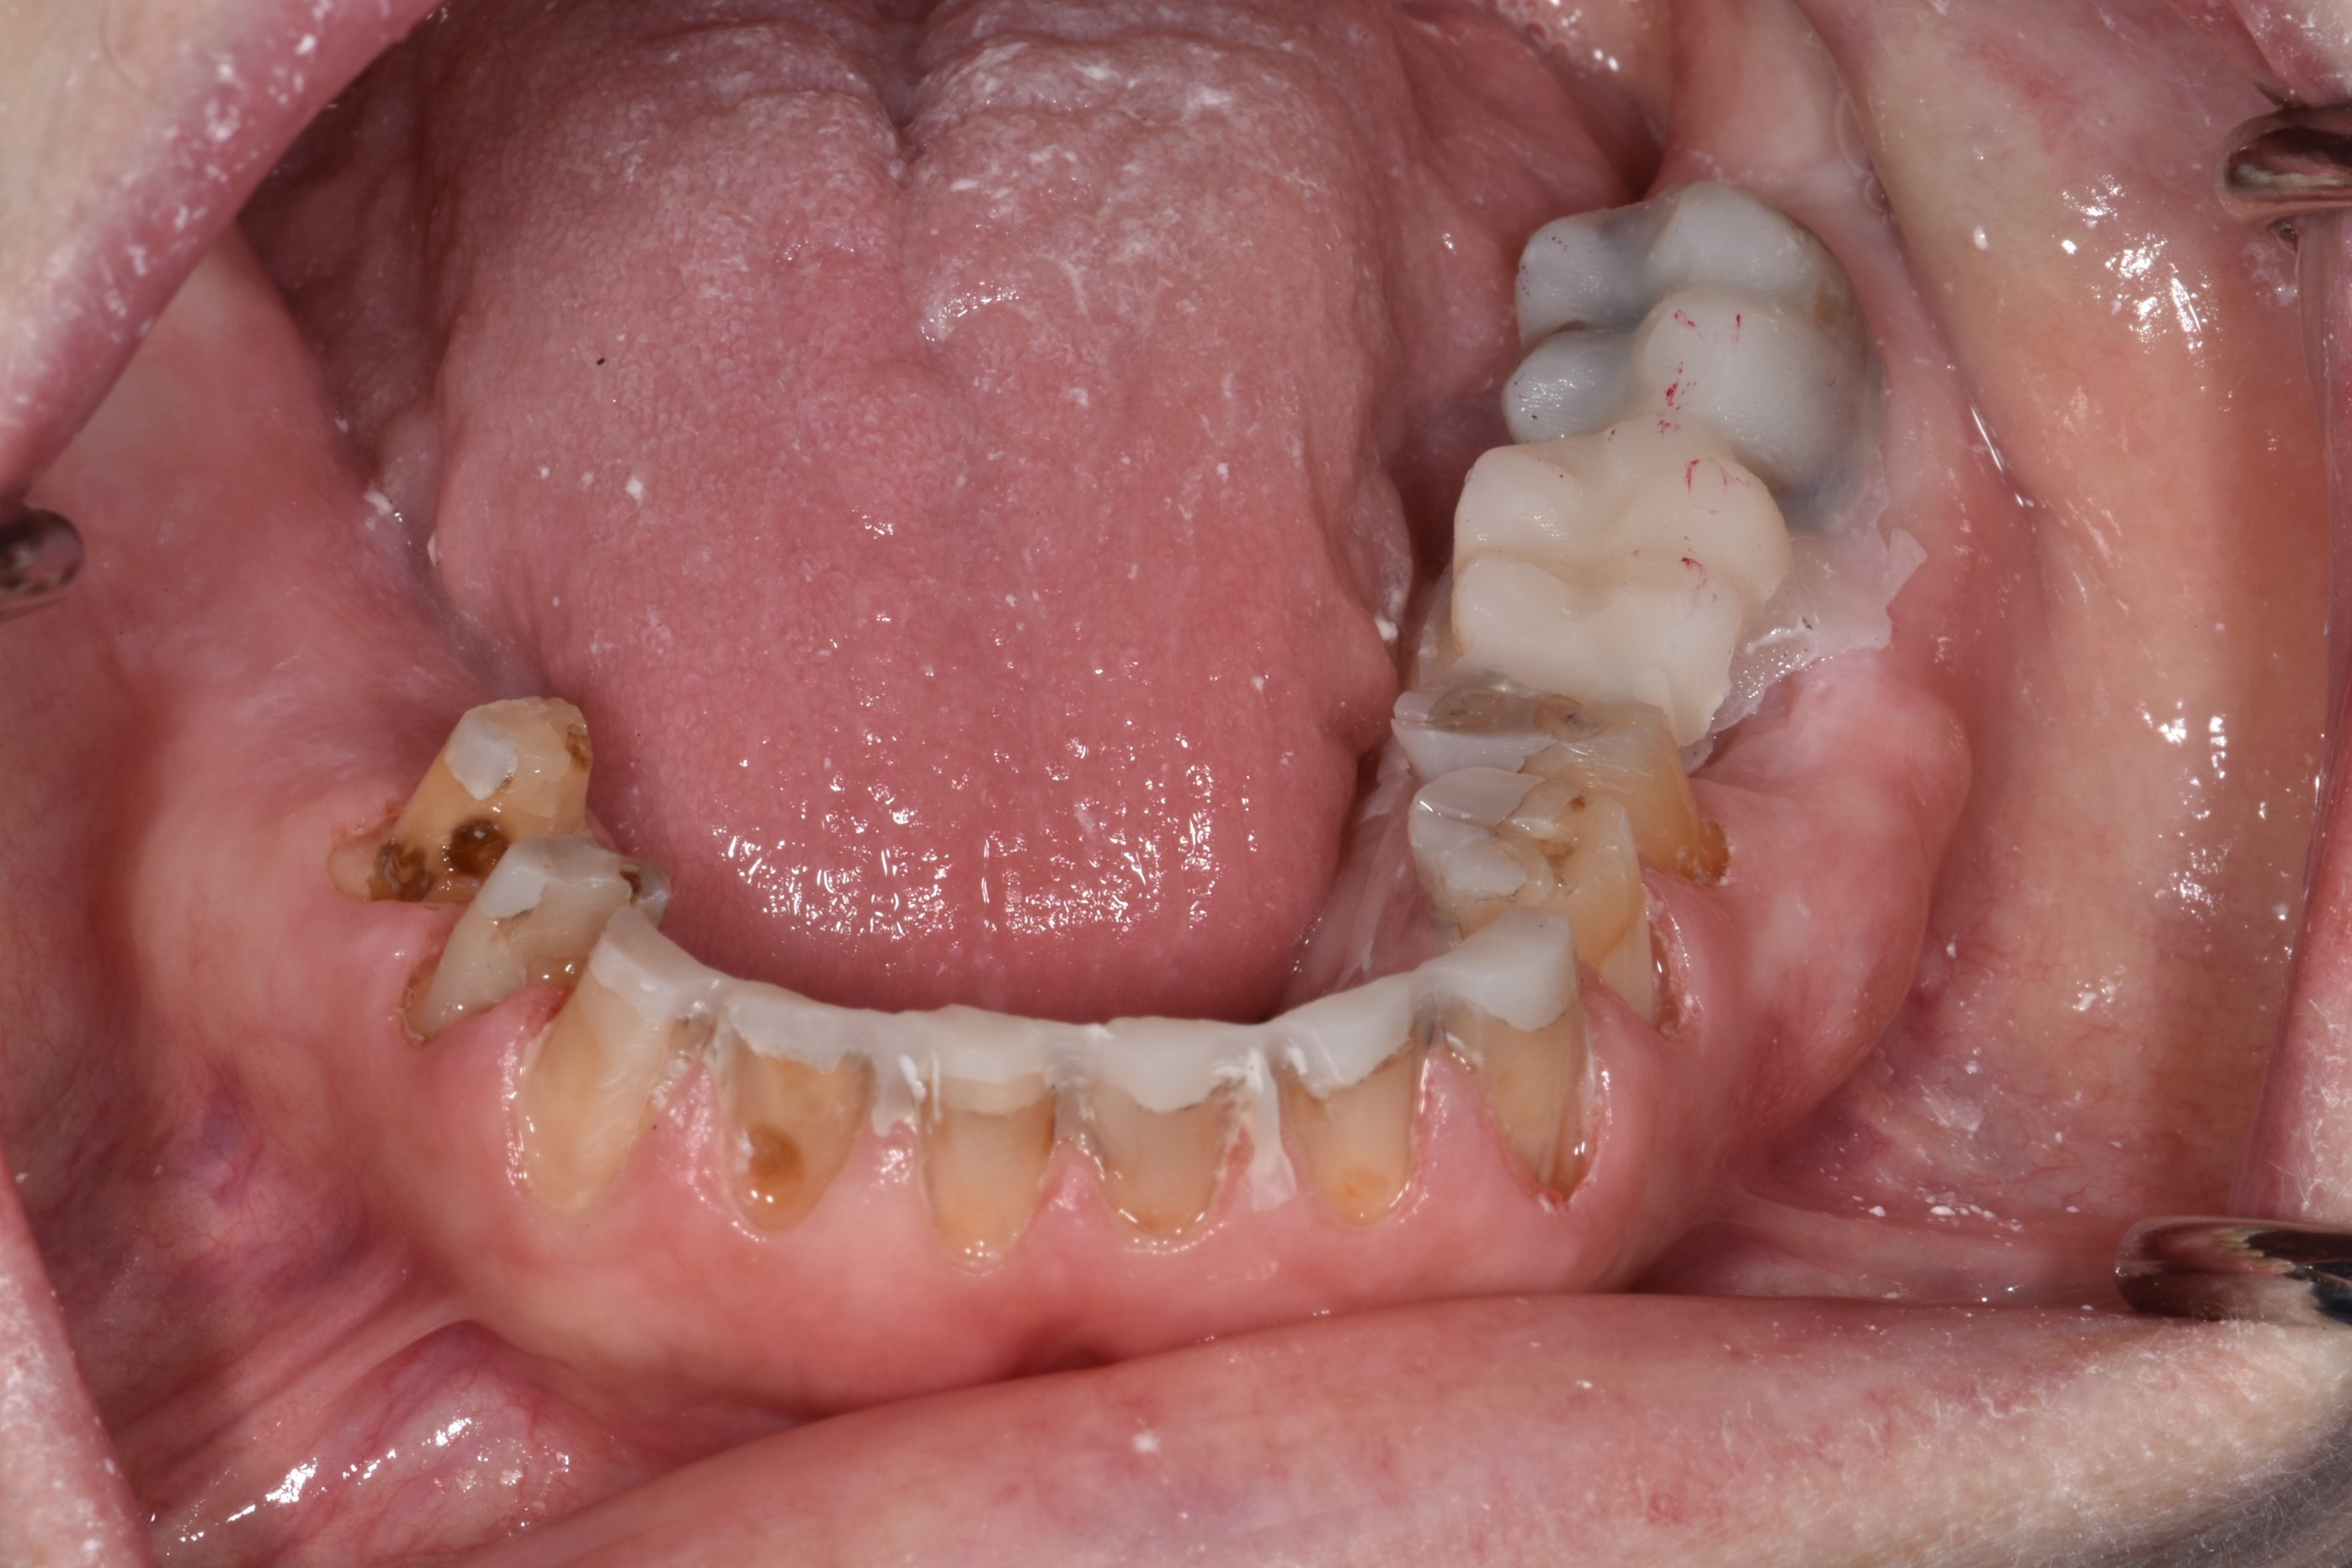

At a clinic treating patients in an underserved population, a 54-year-old female patient presented requesting extraction of all of her teeth and fabrication of dentures for her long-term restorations. The patient had a history of breast cancer, which had been treated with chemotherapy. She believed that full dentures would be an appropriate treatment option for her, owing to the poor state of her oral health and dentition and because she had limited financial resources and did not think that she could afford restoration of her teeth. The patient reported that she had experienced depression and alcohol abuse because of her cancer diagnosis, and that she had neglected her dental care during the course of her cancer treatment, resulting in generalized moderate-to-severe caries with moderate wear due to bruxism (Figure 1 through Figure 5). She also presented with significant staining of her remaining dentition due to the alcohol abuse.

Fig. 3